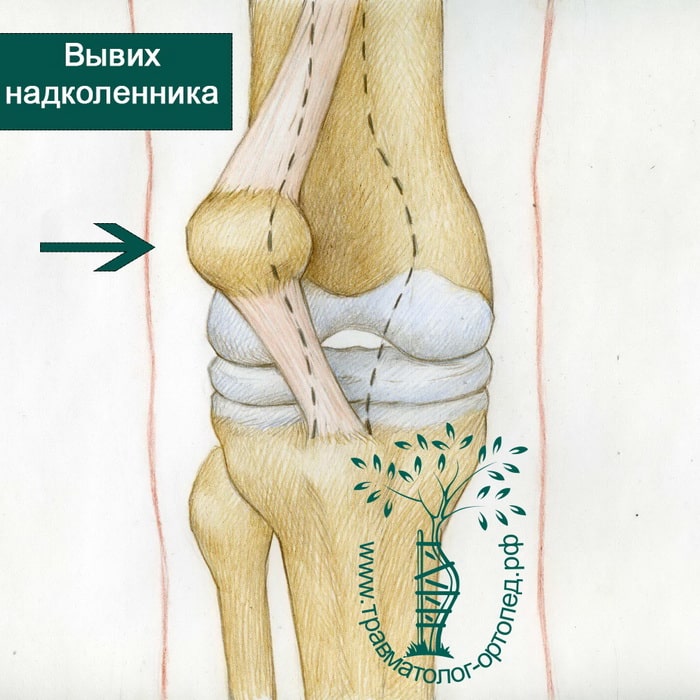

Привычный вывих надколенника лечение в Запорожье клиника ортопедии

Сам по себе вывих надколенника возникает редко, но при врожденных аномалиях коленного сустава или как последствие других травматических повреждений колена вывихи надколенника занимают второе по частоте место среди повреждений коленного сустава. Что значит приставка «привычный»? Она говорит о периодическом повторении такой травмы.

Чтобы произошло смещение надколенника, который мы чаще называем коленной чашечкой, необходима колоссальная нагрузка на ногу. Поэтому чаще всего причиной этой травмы становятся чрезмерно активные занятия спортом и связанные с ними падения на колени, боковые удары в колено (медиальный и латеральный подвывих надколенника), резкие разгибания коленного сустава

Когда такая травма возникает, говорят об остром состоянии. Если через время надколенник снова смещается – это привычный вывих коленного сустава. Нередко он возникает после вправления острого смещения надколенника.

При острой травме надколенника развиваются характерные симптомы. Пациент ощущает резкую сильную боль, коленная чашечка визуально смещается, развивается отек сустава. Обычно ногой очень боль и сложно двигать – согнуть или разогнуть, поэтому нужно немедленно обратиться к врачу.

Привычный вывих колена вызывает менее выраженные проявления. Самые распространенные – это боль в области коленного сустава и чувство нестабильности в колене (колено как будто неустойчиво и при движении не фиксируется).

Под вывихом надколенника подразумевают такое патологическое состояние коленной чашечки, при котором происходит ее смещение, сопровождающееся неприятными и болезненными ощущениями.

Классификация вывихов надколенника

Существует классификация по направленности костного смещения надколенника.

- Боковой — как правило появляется из-за прямой травмы колена при разогнутой голени.

Вывих надколенника можно определить по совокупности совершенно типичных симптомов:

- Резкая и достаточно сильная боль.

- Надколенник изменяет свое положение, а так же смещается относительно своего положения.

- Невозможно опереться на ногу, согнуть ее или разогнуть.